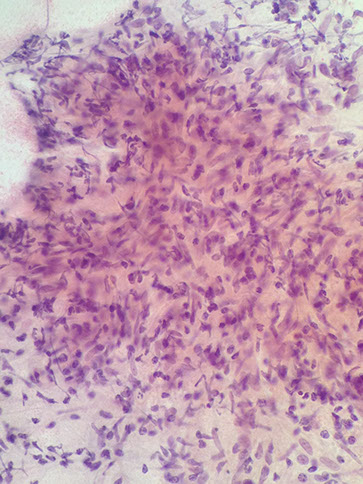

Medullary Carcinoma

Seen more often in younger women (10% younger than 35 years of age).

- Presents as a soft round mobile mass that can be mistaken clinically for fibroadenoma.

FNA shows a cellular specimen composed of large pleomorphic malignant cells arranged singly and in loose syncytial aggregates

Lymphocytes and plasma cells are numerous in the background

The nuclei are enlarged and pleomorphic with irregular nuclear contours, abnormal chromatin distribution and prominent to macro nucleoli

The cytoplasm is fragile, delicate and lacy with indistinct cell borders.

Occasional naked nuclei can be seen in the background (not to be confused with myoepithelial nuclei)